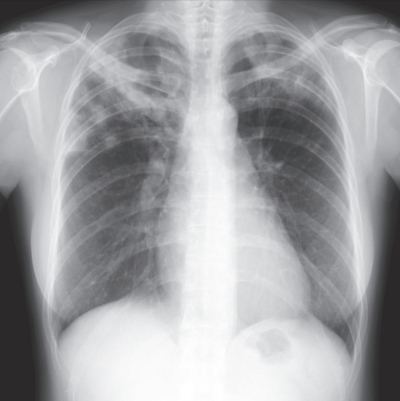

意識は清明。身長156cm、体重40kg。体温37.3℃。脈拍84/分、整。血圧124/82mmHg。呼吸数16/分。SpO2 98%(room air)。心音に異常を認めない。呼吸音は両側でcoarse cracklesを聴取する。来院時の胸部エックス線写真と胸部造影CTを別に示す。